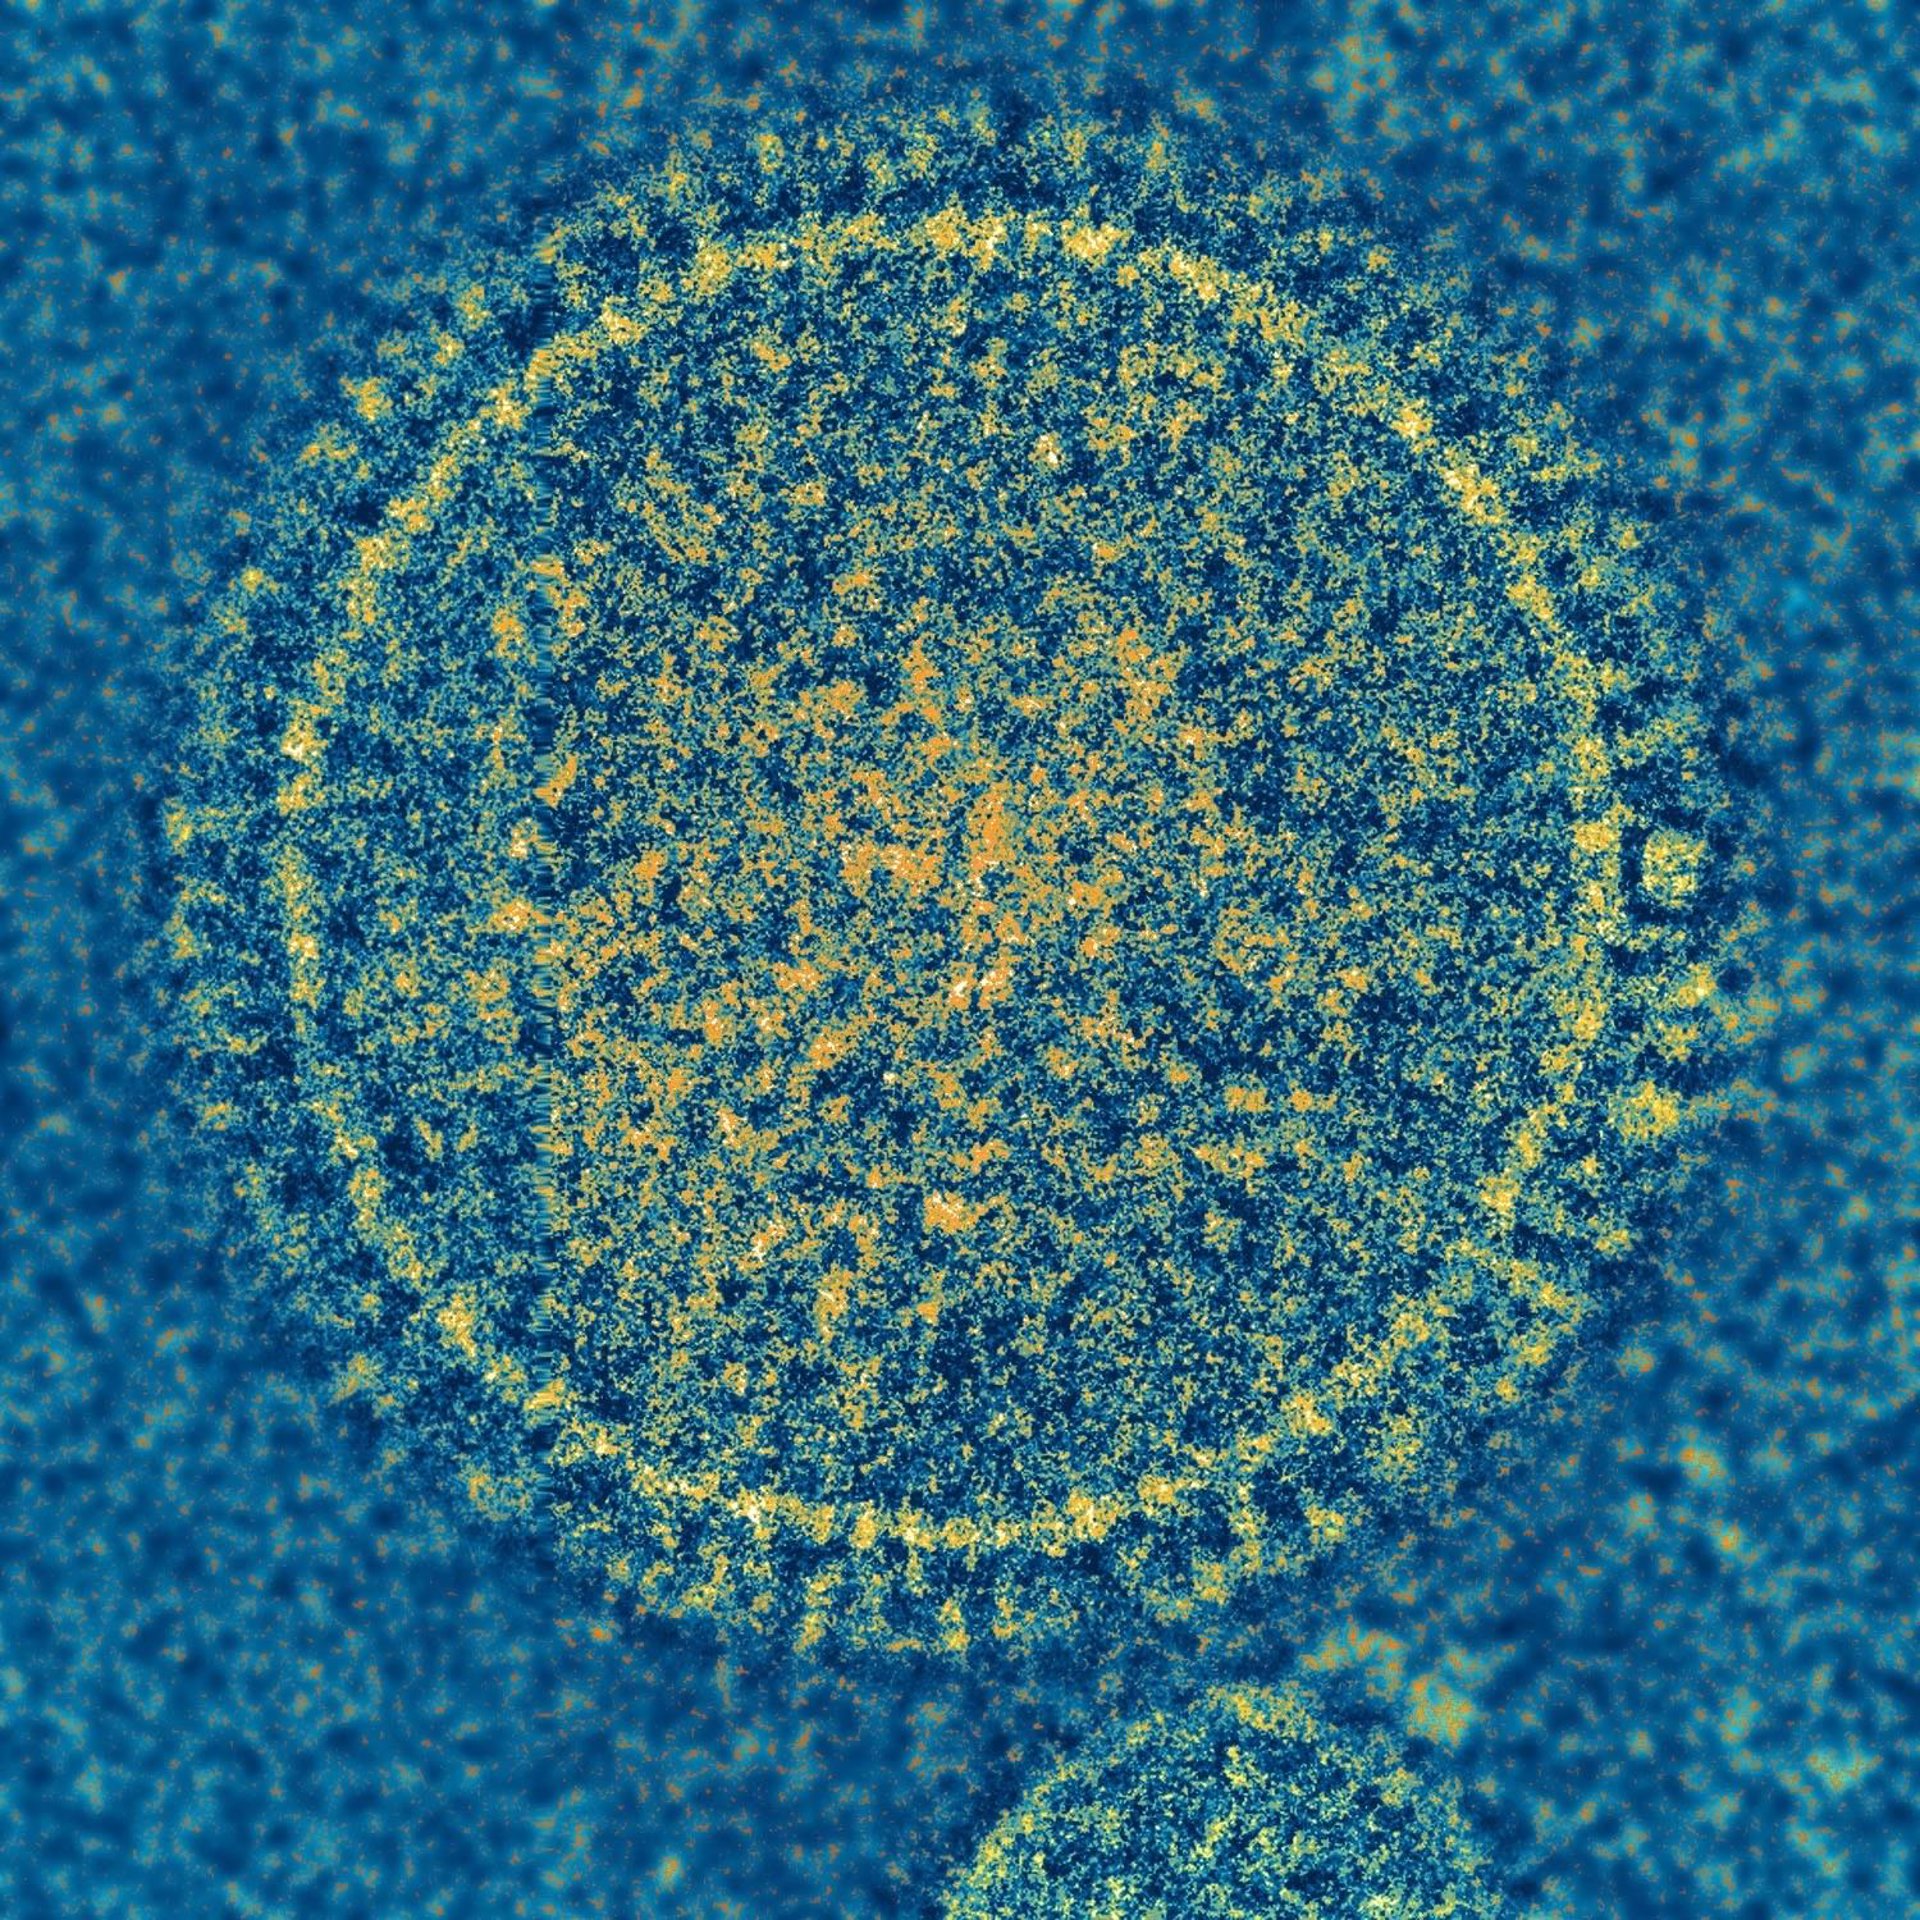

Descubren nuevas pistas sobre el virus respiratorio común

Virus sincitial respiratorio

NIAID

A la edad de 2 años, la mayoría de los niños han sido infectados con el virus sincitial respiratorio (RSV, por sus siglas en inglés), que por lo general sólo causa síntomas leves de resfriado. Pero las personas con sistemas inmunológicos debilitados, como los lactantes y los ancianos, pueden sufrir complicaciones graves, como neumonía y, en algunos casos, la muerte.

Ahora, científicos que estudian el virus, dirigidos por investigadores de la Facultad de Medicina de la Universidad de Washington en St. Louis, Estados Unidos, han encontrado pistas sobre cómo el RSV provoca la enfermedad cuando mapearon la estructura molecular de una proteína del virus que interfiere con la capacidad del cuerpo para combatir el virus. Conocer la estructura de la proteína les ayudará a entender cómo el virus impide la respuesta inmune, lo que podría llevar a una vacuna o un tratamiento para esta infección común.

Sin embargo, para las personas con sistemas inmunológicos debilitados, la lucha contra el virus sincitial respiratorio puede ser difícil porque el virus puede resistir. Los científicos saben desde hace mucho tiempo que una proteína RSV no estructural es clave para la capacidad del virus de evadir la respuesta inmune; pero se desconocía la estructura de esa proteína, llamada NS1. Sin ver cómo era la proteína, los científicos no podían determinar exactamente cómo interfería NS1 con el sistema inmunológico.

"Es una proteína enigmática, todo el mundo piensa que hace muchas cosas diferentes, pero nunca hemos tenido un marco para estudiar cómo y por qué la proteína hace lo que hace", afirma el coautor principal Gaya Amarasinghe, profesor asociado de patología e inmunología. Leung, Amarasinghe y sus colegas utilizaron la cristalografía de rayos X, una técnica que consiste en cristalizar la proteína, rebotar los rayos X contra ella y analizar los patrones resultantes, para determinar la estructura tridimensional de NS1.